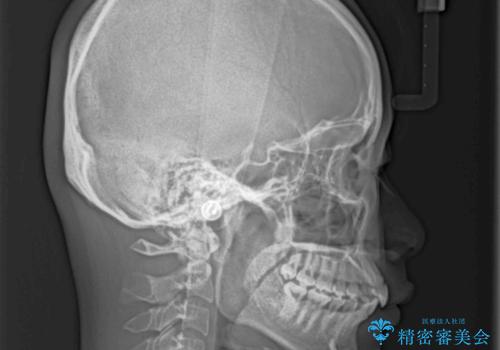

- 前歯の叢生と口元の閉じにくさを気にして来院された患者様です。

奥歯の咬み合わせを見ると、上顎が下顎に対して相対的に前方にありました。

口元の閉じにくさを改善するためには、上顎臼歯を後方に移動させた咬み合わせにする必要があります。

インビザライン単体で改善することも可能ですが、達成する可能性が高くないため、カリエールディスタライザーという補助装置を併用して、より確実性を上げることとしました。

奥歯の咬み合わせを改善しながら、並行してインビザラインで歯列を整えることとしました。